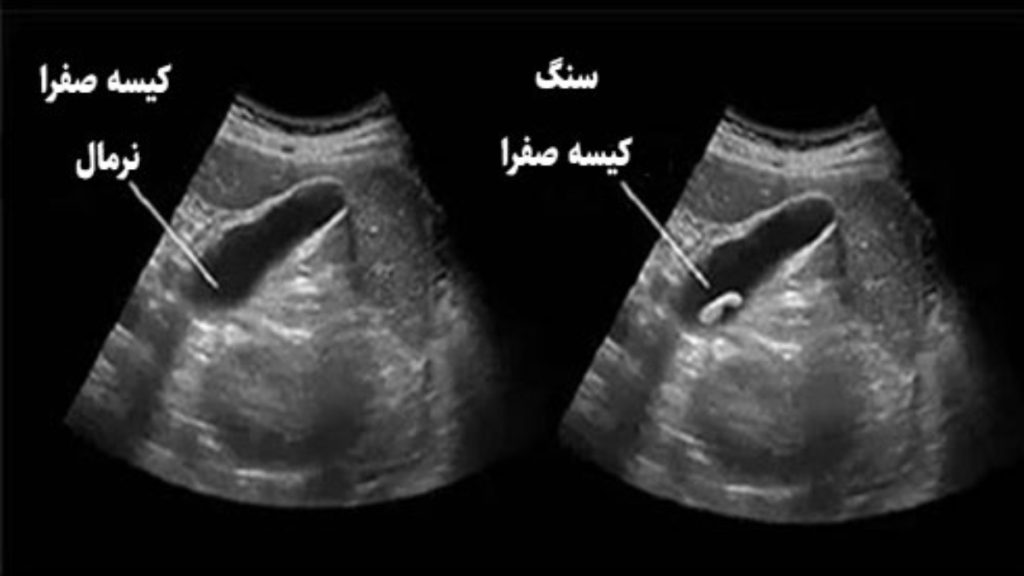

تفسیر جواب اندوسونوگرافی کیسه صفرا - کیسه صفرای نرمال در مقابل سنگ کیسه صفرا